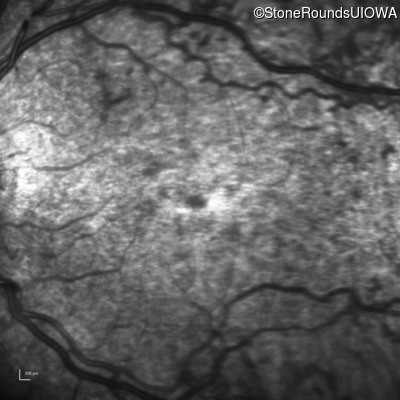

Infrared Fundus Photograph - Right - 20/200 +1

Exemplar